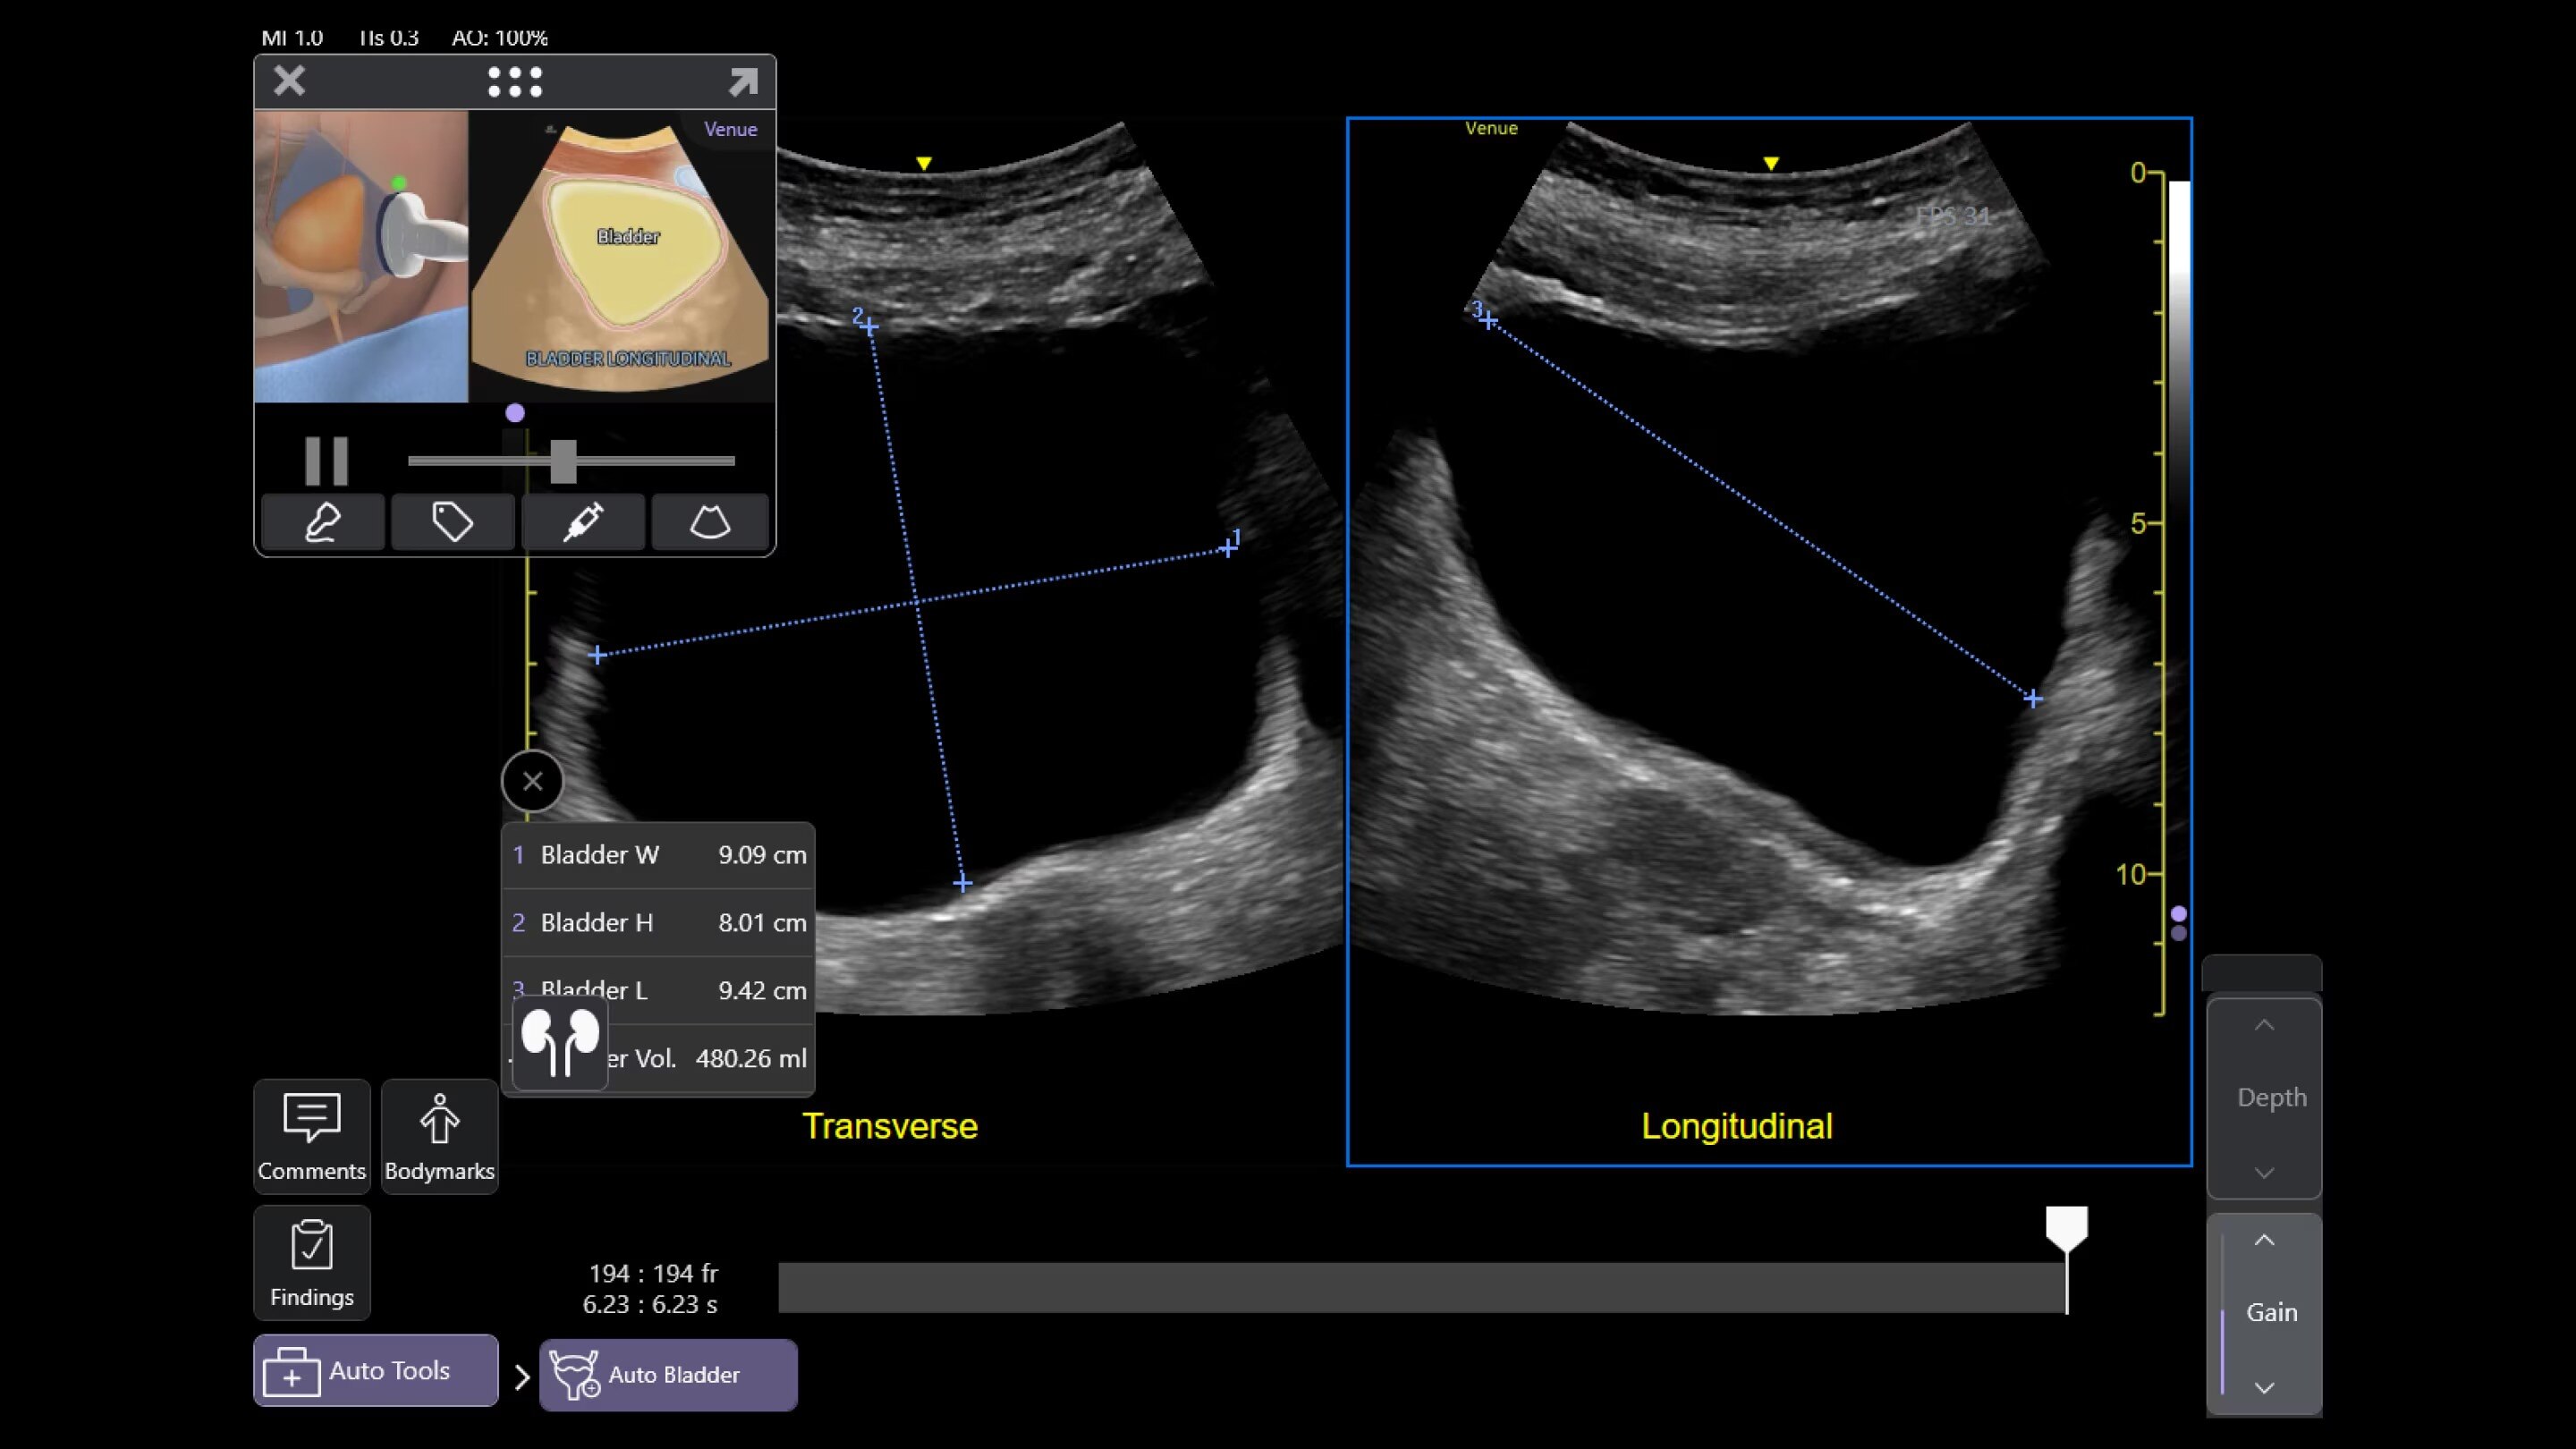

Quickly assess kidneys and the bladder with Renal Diagram

Simplify documentation and easy follow up for patients with suspected hydronephrosis. No need to type findings; simply assign a label from a pre-populated list that correlates with images.